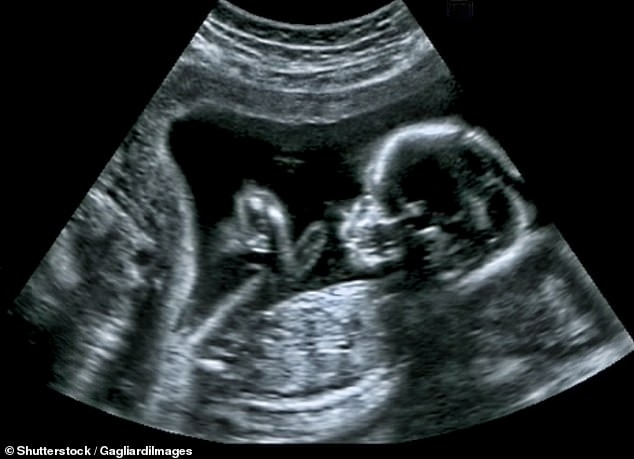

“早知如此我肯定流产!” 一名澳洲母亲生下患有唐氏综合症的婴儿后,将医生和医疗公司全部告上法庭。 2014年,夫妻二人决定提起诉讼,将全科医生、超声医生、做形态学检查的公司和做唐氏综合症风险评估的组 ...